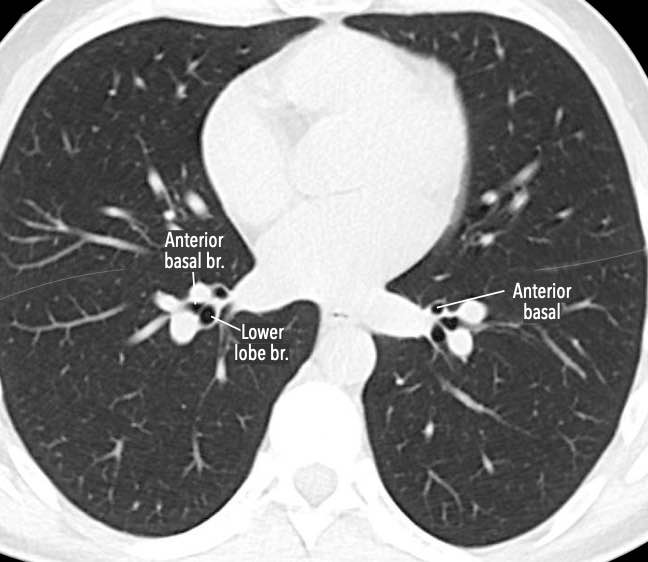

Phế quản trên CT

Cuộn qua các hình ảnh để quan sát khí quản phân chia thành phế quản chính phải và trái, sau đó tiếp tục phân chia thành các phế quản thùy và phế quản phân thùy.